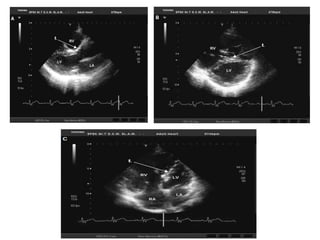

Apical four-chamber view (systolic frame) showing measurement of TV tethering height

• It is important to note that with TV annular dilatation, the

regurgitant jet needs to be assessed from multiple

echocardiographic windows to minimize errors from under

appreciating the regurgitation.

• In practice, the vena contracta width is the most reliable

parameter to quantify TR.

• Zoghbi et al. defined a vena contracta width > 0.7 cm as

indicating severe TR.

• Both the proximal isovelocity surface area and vena

contracta methods are reported to be more accurate for

central jets as opposed to eccentric jets.

• However, a 20% to 30% underestimation of TR severity can

occur using the proximal isovelocity surface area or jet area

method.

• In addition to evaluating the TR jet by color Doppler and

measuring the vena contracta width, the size of the inferior

vena cava (IVC) and right atrium and hepatic venous flow

reversal are used to assess TR severity.

• However, these indirect signs are also influenced by other

factors, such as RV compliance, RV preload, and atrial

tachyarrhythmias.